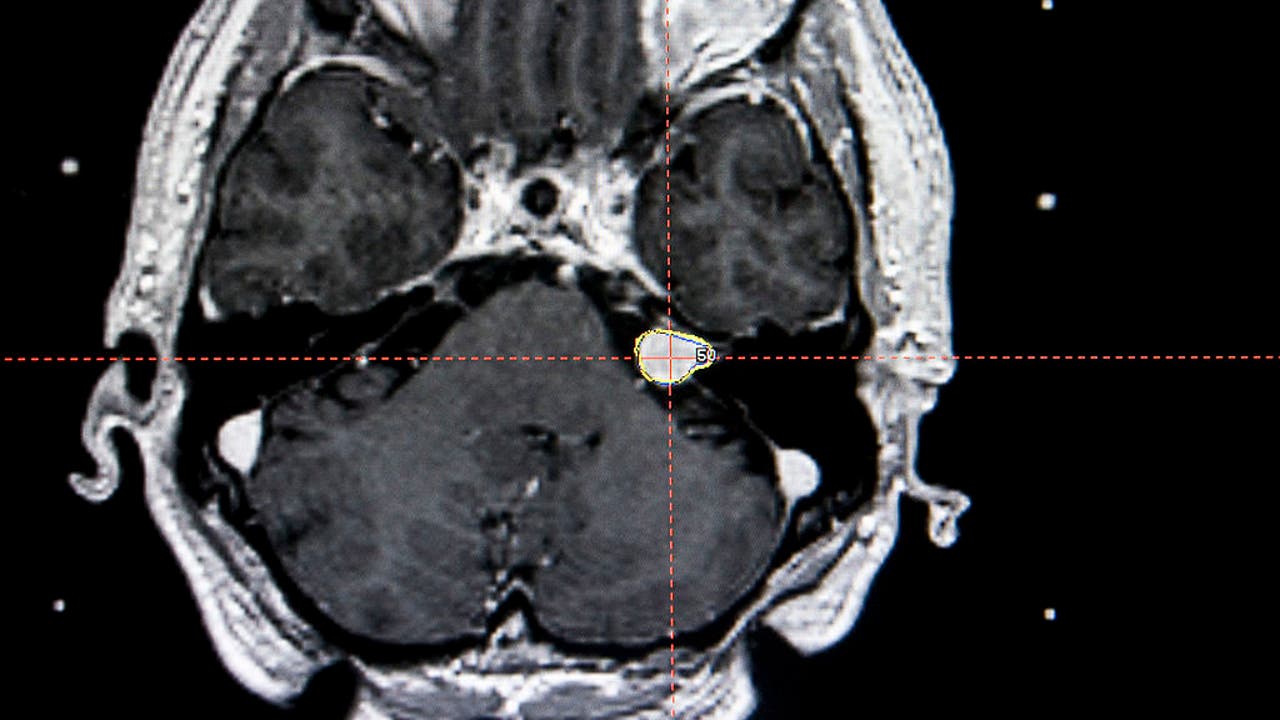

Acoustic Neuroma, Mri

Photo Essay At The Regional Hospital Complex Of Lille, France, Hospital Roger Salengro, Department Of Neurosurgery, Gamma Knife. Photo Essay At The Regional Hospital Complex Of Lille, France, Hospital Roger Salengro, Department Otreatment Of An Acous